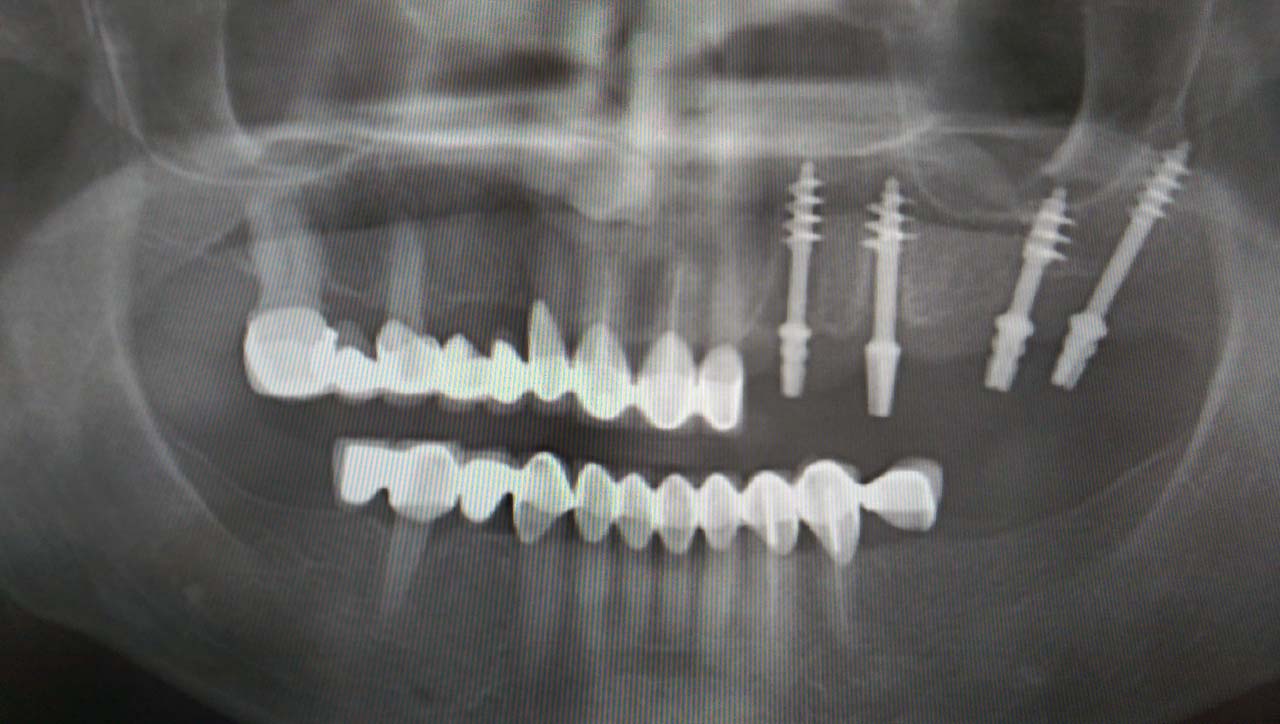

Teljes alsó,felső állcsont helyreállítása azonnal

terhelhető implantátumokkal és porcelán hidakkal.